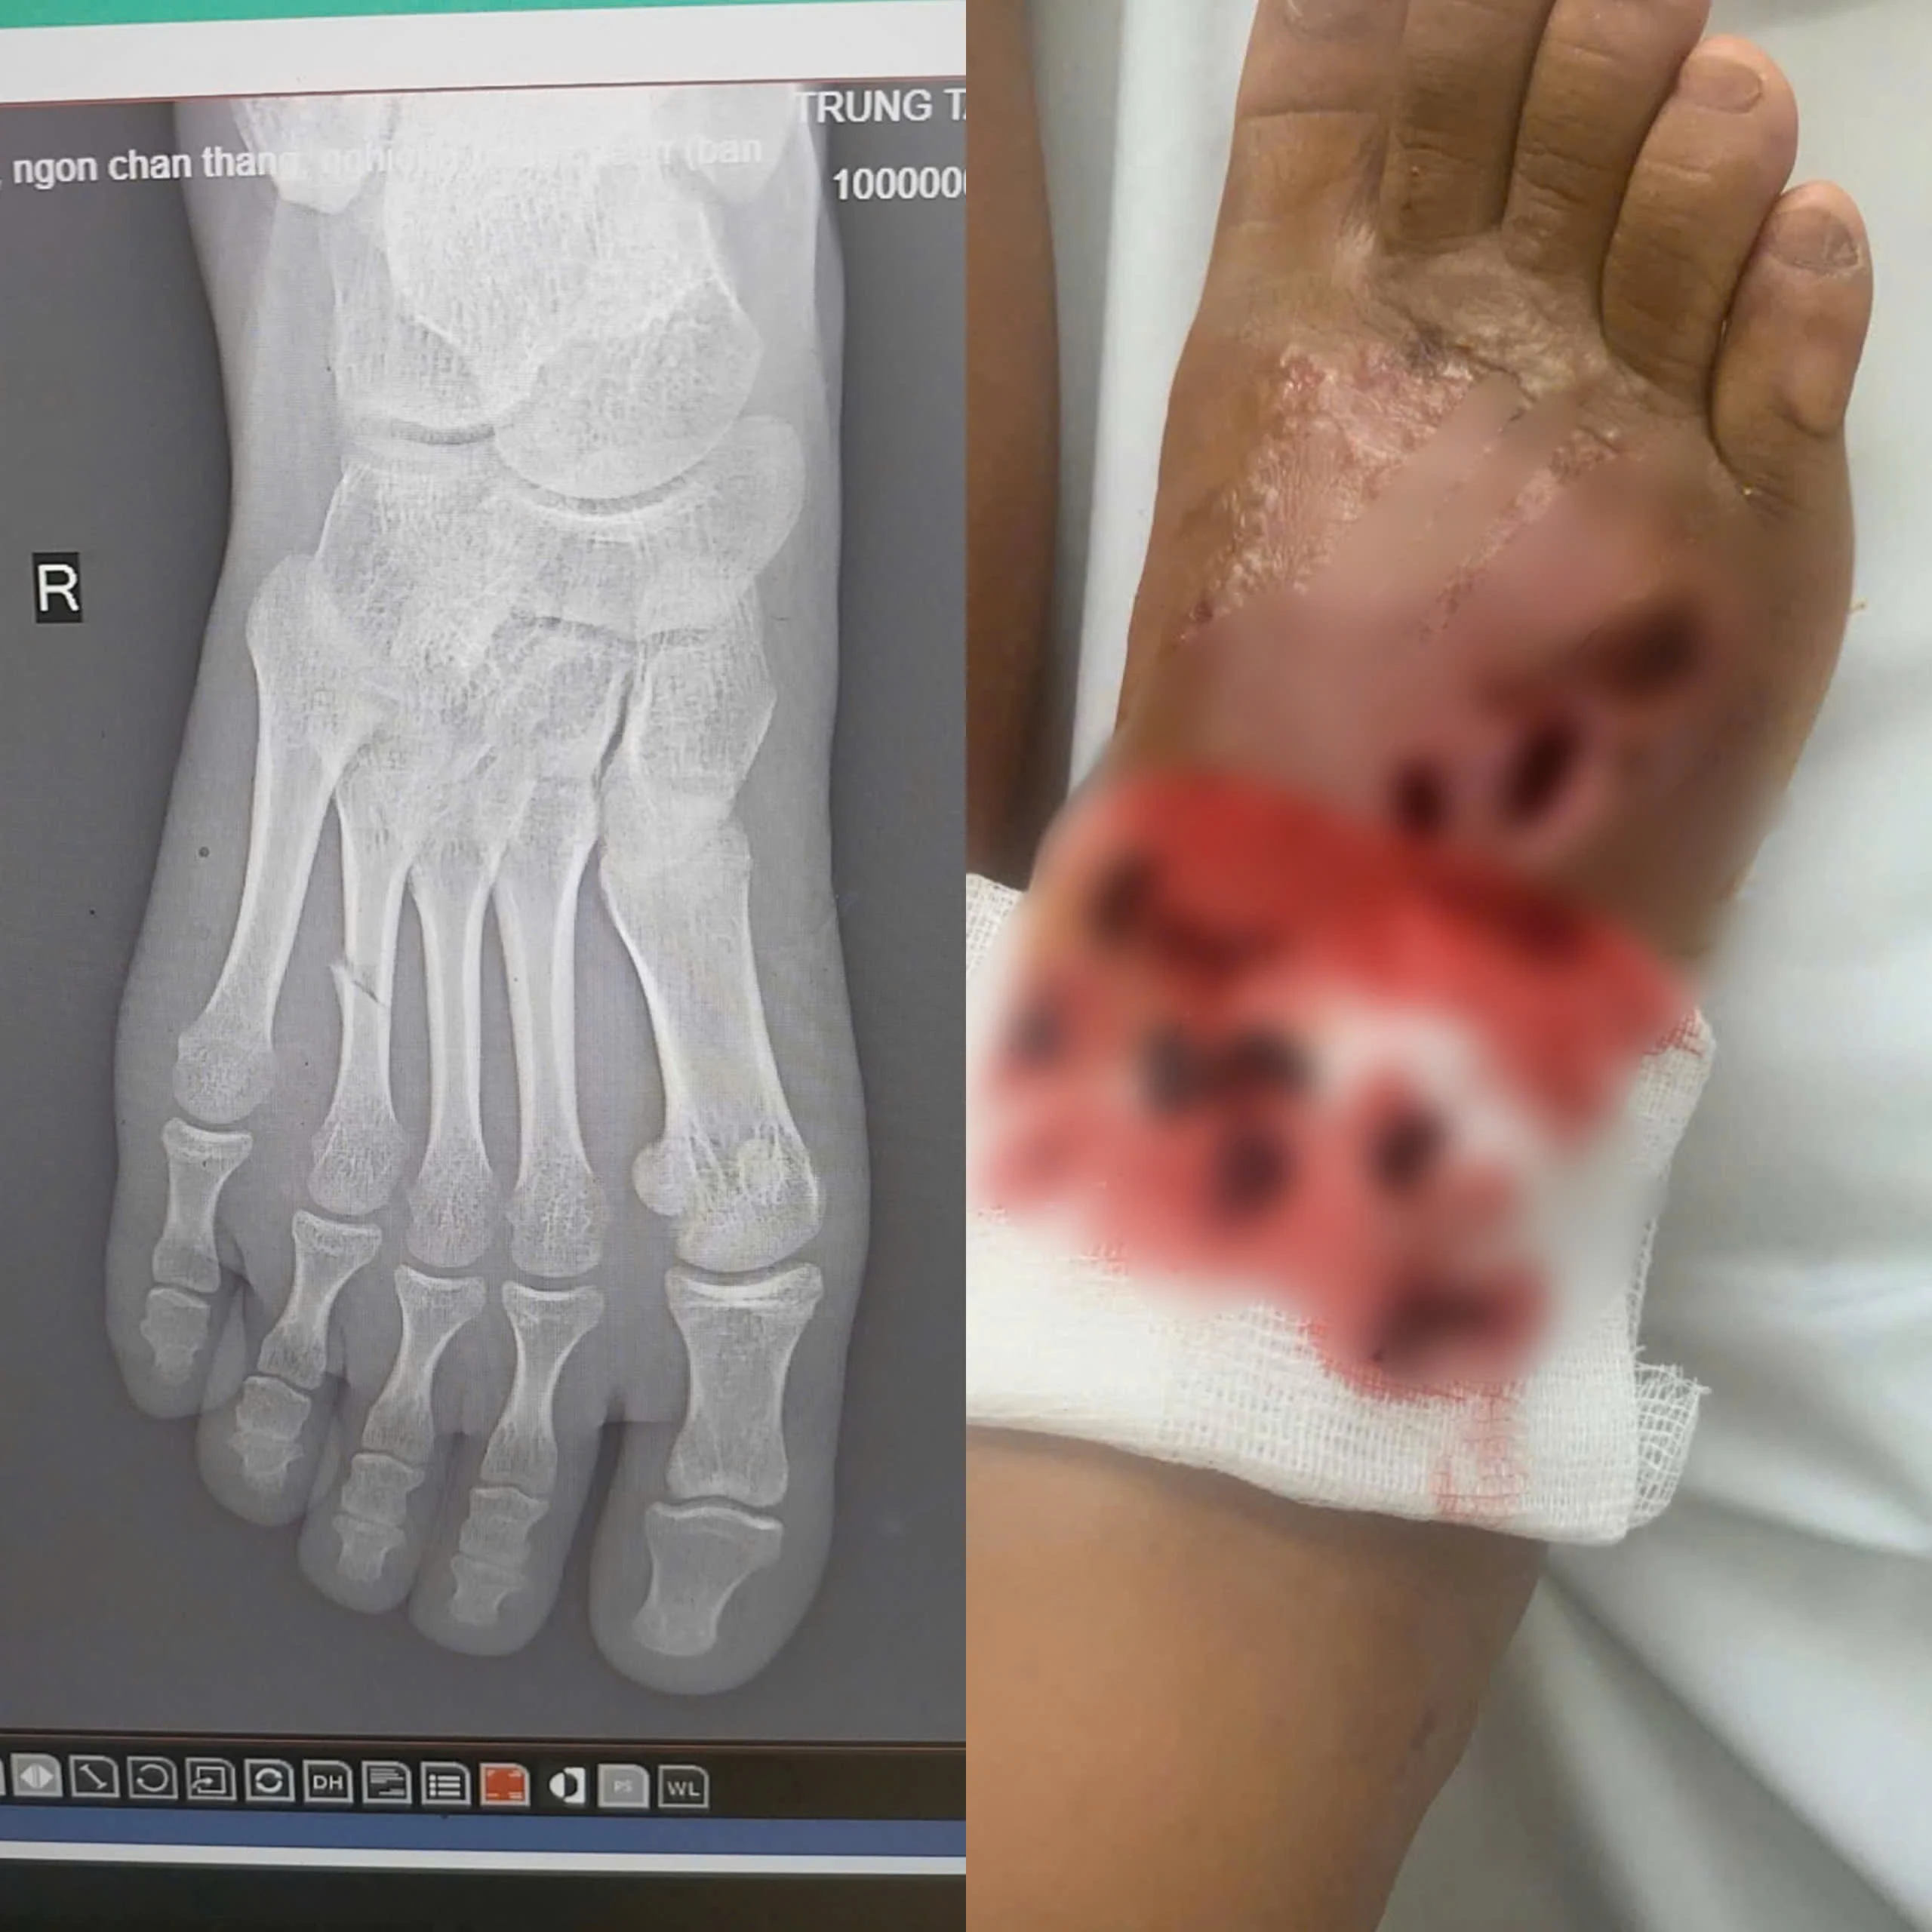

Trung tâm Y tế huyện Đoan Hùng vừa tiếp nhận bệnh nhân N.T.T.T, 14 tuổi, trú tại xã Quyết Thắng, huyện Sơn Dương, tỉnh Tuyên Quang, trong tình trạng bàn chân phải sưng nề, đau nhức dữ dội, có nhiều ổ loét sâu đang hoại tử, dịch mủ chảy ra và có dấu hiệu nhiễm trùng lan rộng sau khi tự điều trị bằng phương pháp bó thuốc nam tại nhà.

Các bác sĩ thay băng cho bệnh nhân nhiễm trùng nặng do bó thuốc nam

Trước đó 14 ngày, bệnh nhân T bị ngã gãy chân, thay vì đến bệnh viện để được điều trị kịp thời, gia đình người bệnh lại chọn phương pháp bó thuốc nam tại nhà. Chỉ sau 5 ngày, vết thương đã bắt đầu sưng to, đau nhức dữ dội, chảy dịch mủ và có mùi hôi. Sau khi thấy triệu chứng tiến triển nặng hơn, gia đình đưa cháu tới khám tại Trung tâm Y tế huyện Đoan Hùng.

Hình ảnh bàn chân bệnh nhân khi vào viện